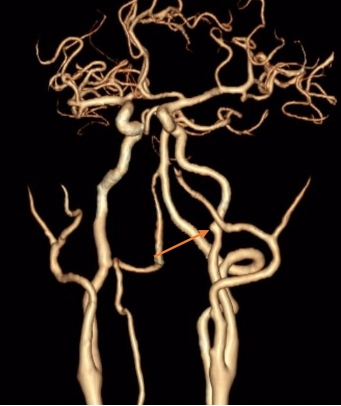

入院后,治疗团队为其完善血管头颈部CTA检查,发现肿瘤包绕颈内动脉,左侧颈内动脉肿瘤包绕处可见假性动脉瘤,基底动脉环显示左侧后交通动脉粗大。

箭头所指为假性动脉瘤